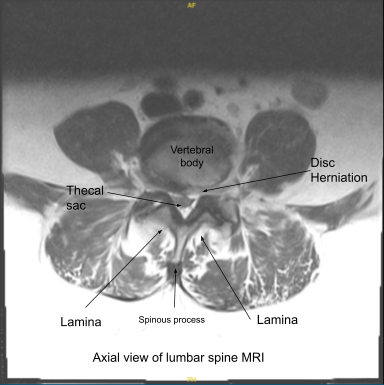

The patient presented with severe radicular pain on the left lower extremity, which was not relieved with conservative treatment and the patient was admitted to the hospital where magnetic resonance imaging (MRI) was done, which showed an extruded and herniated disc of left L4-5. The patient was also having weakness in the L5 myotome on the left.

We discussed systemic complications including blood clot, cardiac, pulmonary, and neurological complications including blindness and death. The patient understood and signed an informed consent. MRI findings supported the diagnosis of spinal canal stenosis and neural foraminal narrowing.

Axial view of Lumbar Spine MRI